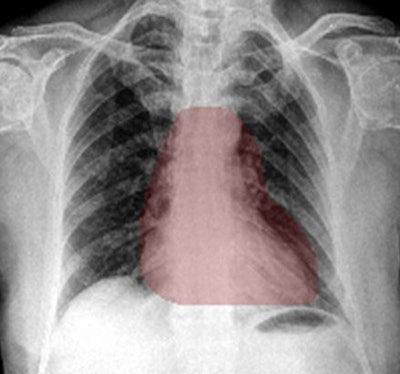

The researchers believe that the algorithm's clinical utility is enhanced by its ability to generate heat maps.

"[These heat maps] have literally allowed us to see through the algorithm's 'eyes,' " Govil said.

The algorithm can generate heat maps using two methods: occlusion visualization and integrated gradients. The occlusion visualization technique color codes an image patch that is considered to be the most significant abnormality on the image, while the integrated gradients method accounts for the sensitivity of each pixel prediction and obtains an approximate attribution score for each pixel.

These heat maps can help win over doctors who may be skeptical about the benefits of deep learning and AI, according to Govil.

"If you show them the heat maps, there's an immediate confidence that it is looking at what we are looking at," she said.

Heat maps can provide clinical users and those who are validating AI algorithms with visual cues that could make it easier to accept or reject a deep learning-based chest x-ray diagnosis, Govil said. In addition to raising confidence in the machine's ability to analyze complexity, heat maps could also potentially be a means of providing feedback to the trainee computer.